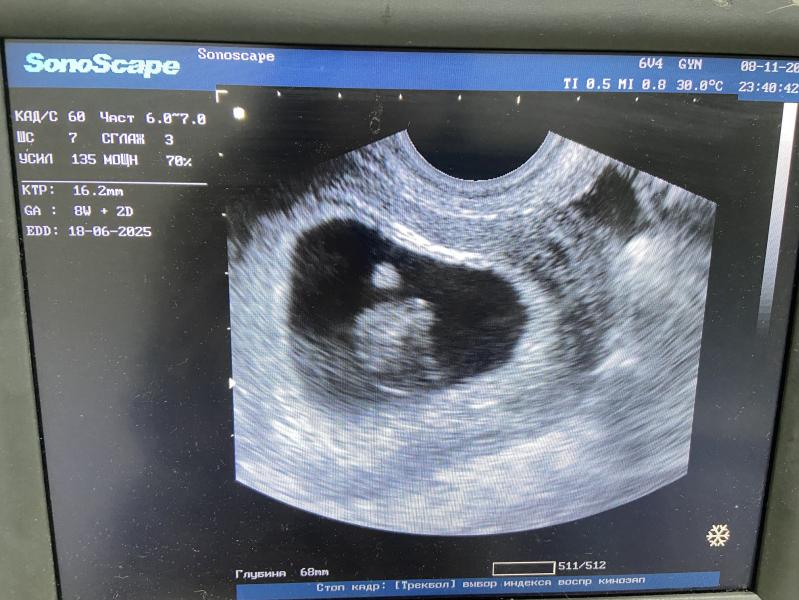

Сказали, что 8 неделя уже (я до сих пор в шоке, т.к. ничего по прежнему не чувствую 😀) ПДР на 18 июня (ох, уж эти неопределенные близнецы) Я сама рачок 🥰